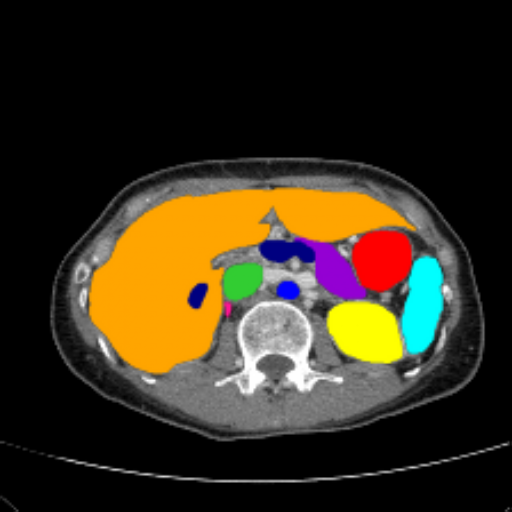

Figure 3 presents a qualitative comparison of segmentation performance on examples from the Synapse, BTCV, ACDC, and ISIC17 datasets. The first two examples (from Synapse) highlight variations in segmentation performance among U-Net, TransUnet, Mamba-Unet, and Swin-Unet. While Swin-Unet performs well in the first example, its performance decreases in the second example, particularly in segmenting the organ highlighted in blue. Additionally, it misclassifies background regions as the class highlighted in orange. In contrast, our approach demonstrates high robustness in segmenting all classes accurately and aligning well with the ground truth masks.

Refer to caption Refer to caption Refer to caption Refer to caption Refer to caption Refer to caption Refer to caption

Slice GT Unet TransUnet Mamba-Unet Swin-UMamba MambaCAFU-V1

Figure 3: Visual comparison of segmentation examples from Synapse (first two examples), BTCV (3-4 examples), ACDC (5th example) and ISIC17 (last example). Columns: input slice, ground truth, Unet, TransUnet, Mamba-Unet, Swin-UMamba, and MambaCAFU-V1.